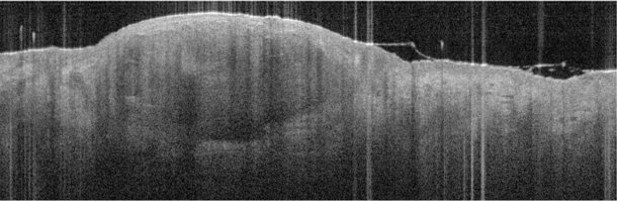

Click to view moreLeading imaging technologies advancing non-invasive dermatological diagnostics